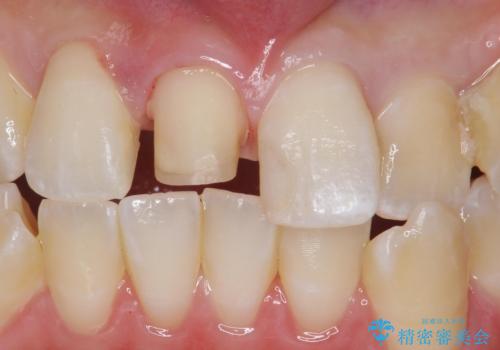

前歯の色が気になる。オールセラミッククラウンでのやり替え

- 前歯のかぶせ物の色が気になるとのことで来院された患者様です。

セラミッククラウンで作り変えていきます。

色・形ともに改善され、大変喜んでいただけました。